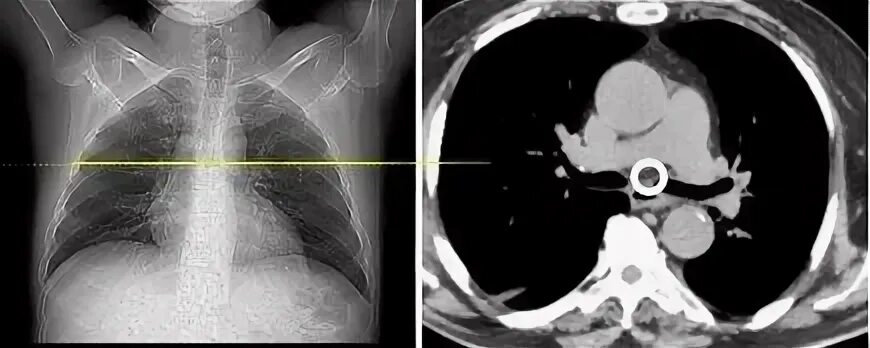

Легочный ствол на кт